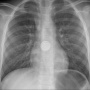

È quanto ha rischiato il piccolo Elias*, un bimbo di dieci mesi che aveva improvvisamente smesso di mangiare. I genitori lo hanno portato al pronto soccorso dell'ospedale pediatrico, dove una radiografia ha permesso d'identificare un corpo estraneo all'interno dell'esofago. Un intervento d'urgenza sotto anestesia totale ha permesso di rimuoverlo: si trattava di una pila a bottone. Sembra che il bambino l'abbia tolta da un telecomando.

Nell'esofago del piccolo Elias ha avuto inizio una reazione chimica, che ha causato un'ustione. Ma il bambino ha avuto fortuna: la rapida decisione di portarlo in ospedale e l'immediato intervento hanno permesso di limitare le conseguenze.